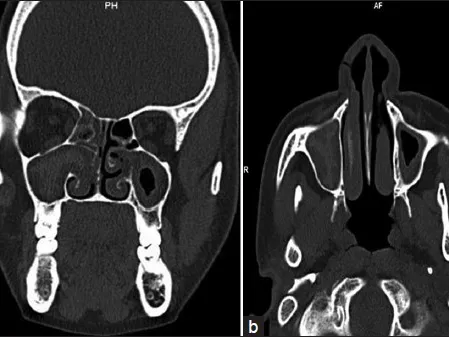

Paranasal Sinuses CT

This radiology reporting course focuses on the complex anatomy of the paranasal sinuses (PNS). Multiple normal variants on PNS are important for presurgical assessment. By completing the course, you will know how to create detailed and concise structured CT PNS reports.

This course on paranasal sinuses will focus on detailed CT anatomy and important paranasal sinus landmarks. You will learn how to prospectively identify important normal variants that predispose patients for surgical complications and how to easily navigate through the complex structures of a PNS CT.